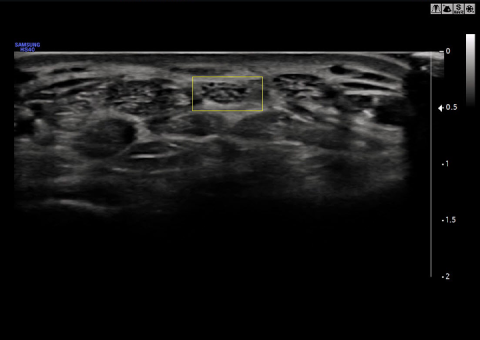

With pinpoint precision, NeedleMate+™ delineates needle location when performing interventions such as nerve blocks. Improved accuracy and efficiency in the procedure are possible with beam steering added to NeedleMate™